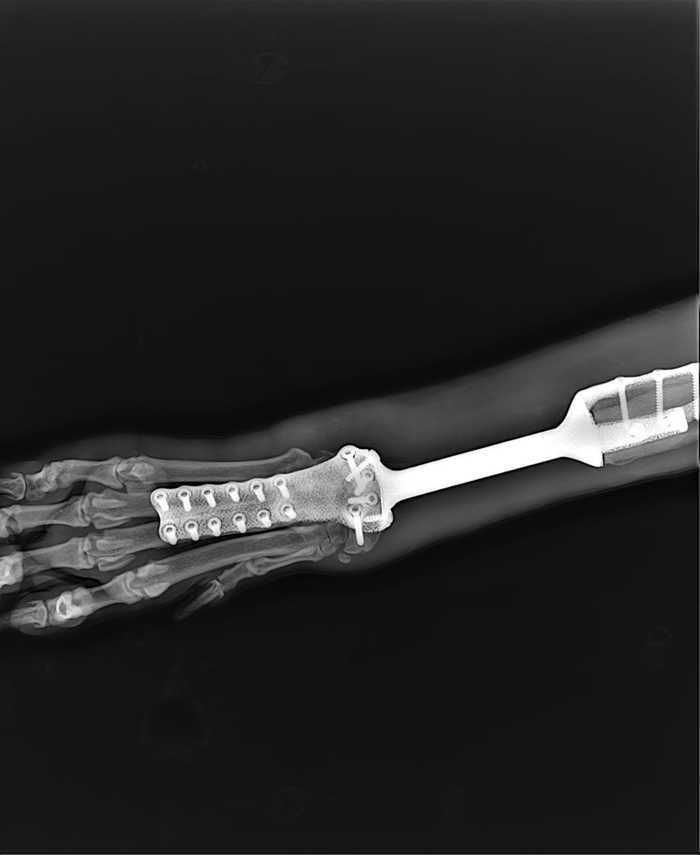

Через несколько дней ребята из организации, где печатали первый протез, напечатали ему пластиковую штуку (я фиг знает как это назвать правильно), которая прикручивалась к остатку титановой ноги. Тут от меня им безмерная благодарность, т.к. мало того, что не взяли ни копейки, так еще и отношение у них к работе выше всяких похвал. Забегая вперед, мы у них еще не раз были, таких болеющих за работу еще поискать. Кому интересно, обязательно все названия напишу.

В общем позвонила опять туда где печатали эту, и отправила им фото произошедшего. Меня успокоили и сказали что все перепечатают по новому без проблем, надо только подождать несколько дней. Когда нога была готова мы поехали ее забирать без Умки. Попытались дома прикрутить а она не садится, никак. Титановая часть чутка поменялась из-за того, что Умка на нее опирался и не входила в старые слепки. Повезли его самого. Ребята подгоняли ему копыто, а он валялся и балдел, все гладят, тискают, внимание. Короче ему понравилось. И стал он вообще красавчиком.